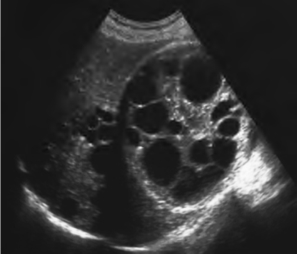

1.33.6六、多囊肾